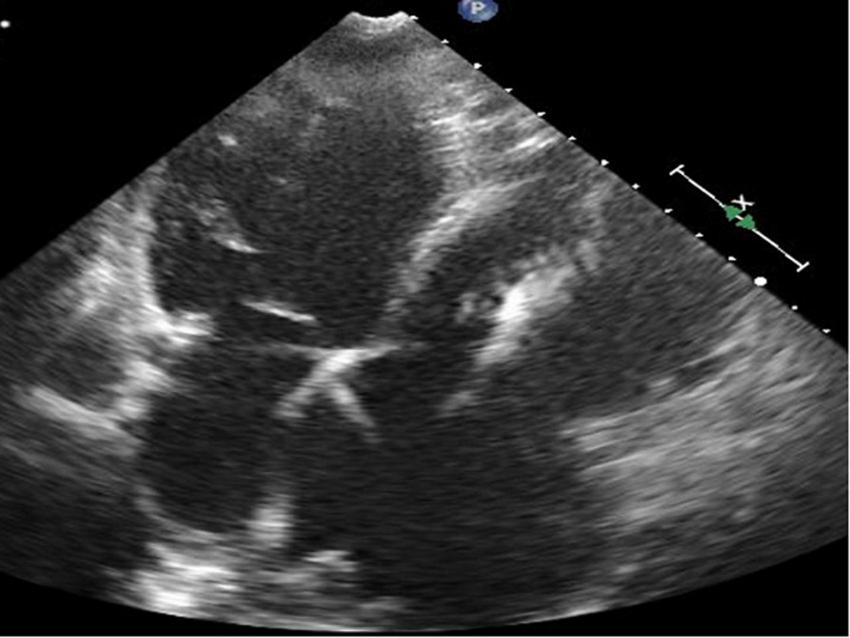

FIGURE 7

Short-axis view at end-diastolic phase of transthoracic echocardiography in Case 4.

FIGURE 8

Four-chamber view at end-systolic phase of transthoracic echocardiography in Case 4. Note that the tricuspid valve does not close at all, and the right atrium is hugely dilated.